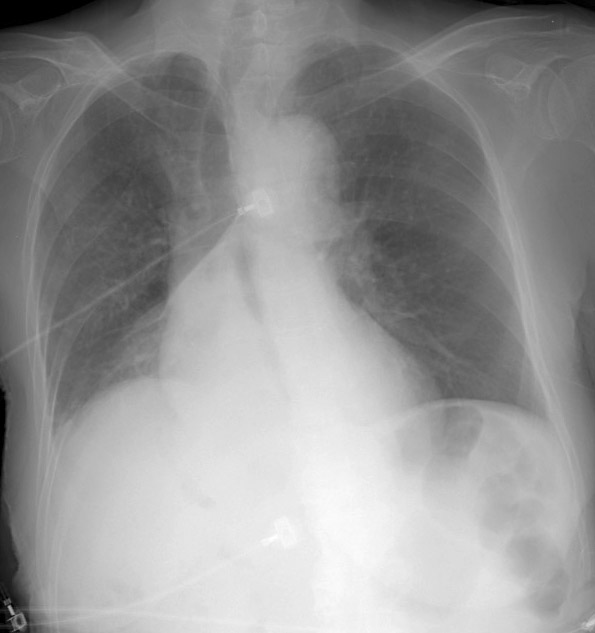

RLL Collapse 2 PA only